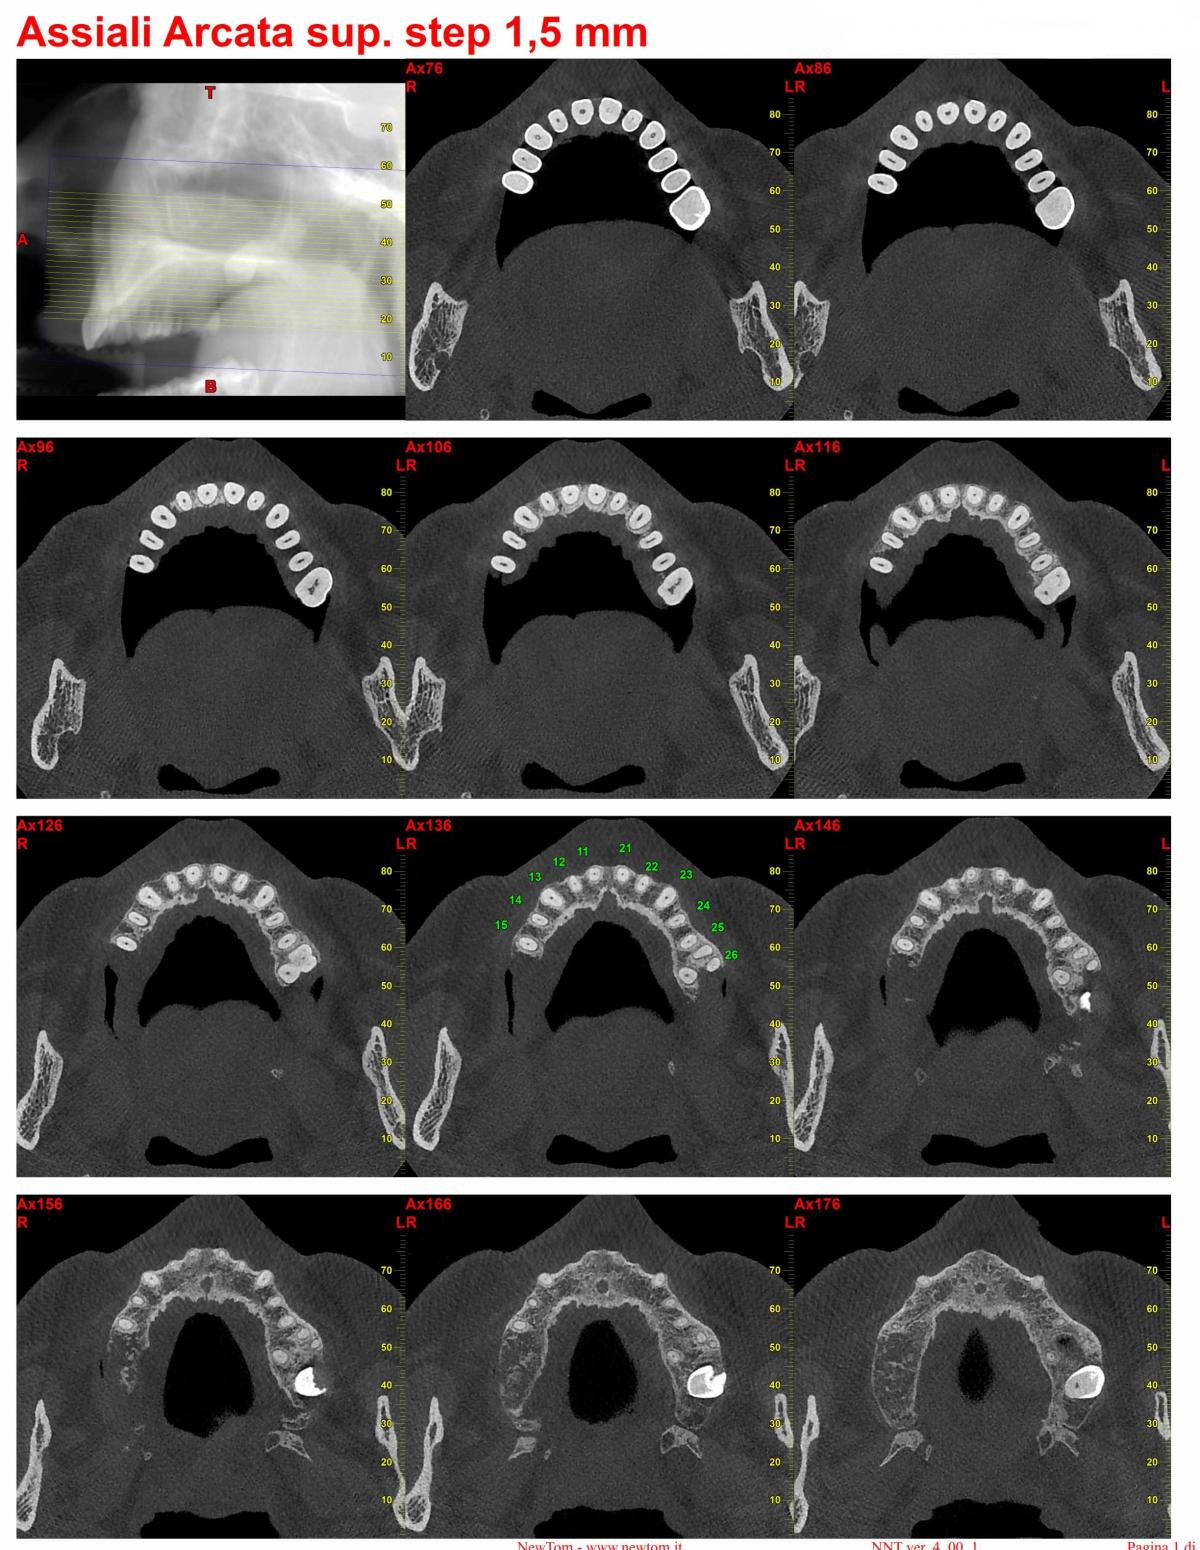

l' esame CBCT evidenzia un' immagine compatibile con pseudocisti antrale

post-729-0-26240300-1384250911_thumb.jpg

post-729-0-56534500-1384250953_thumb.jpg